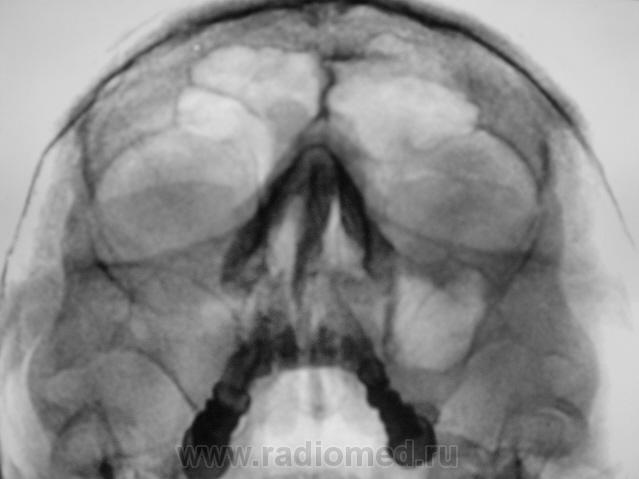

Больше похоже на кисту. Четкий округлый контур с характерным месторасположением. Хотя может и не так все просто)

да,  похоже на кисту, но справа снижена пневматизация верхнечел.пазухи за счет умеренного отека, я бы кисту слева под вопросом написала и направила на контроль

---------------------------------------------------------------------------------------------------------------------------------------------------------------------------------+1: как вариант,  можно предположить, что киста одонтогенного происхождения.

Второй случай. уровень слева,субтотальное затенение справа.киста правой половины лобной.....